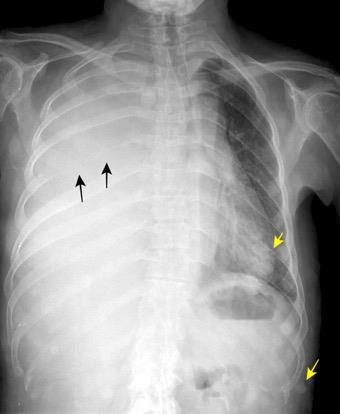

1/30.000 nacimientos

Hipoplasia/ausencia de mama o pezón.

Hipoplasia de tejidos subcutáneos.

Ausencia de la porción costoesternal del pectoral mayor.

Ausencia del pectoral menor.

Ausencia de cartílagos costales o costillas, 2,3 y 4.

Variante: Síndrome de Poland con dextrocardia.

Hipoplasia Art. pulmonar dcha. Atelectasia.

Bansal A, et al. Poland syndrome: a case report. BMJ Case Rep 2017

Mutlu H et al. A variant of Poland syndrome associated with dextroposition. J. Thorac. Imaging. 2007